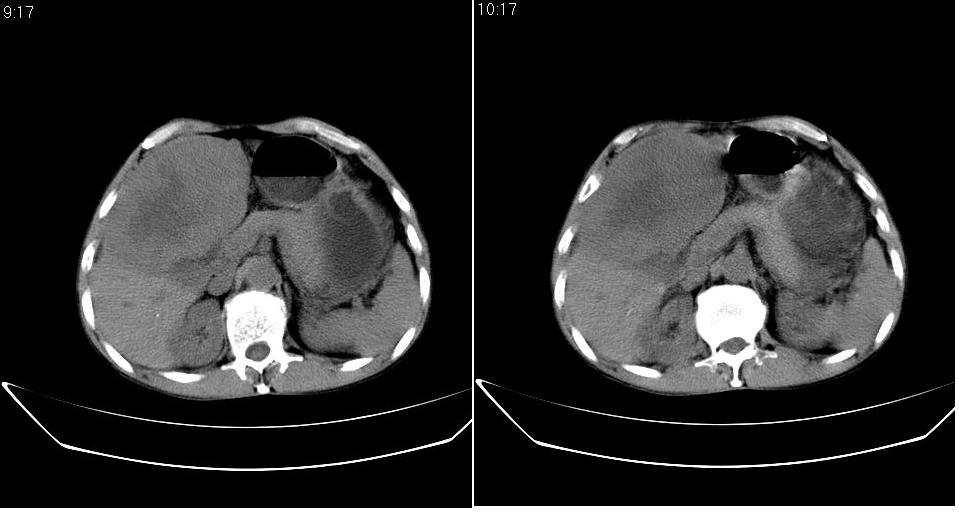

标题: CT20033:上腹部CT平扫

男 66岁,腹疼,b超提示考虑肝癌。

考虑巨块型型肝癌坏死、出血。建议增强。

考虑肝左叶巨块型肝癌可能性大;建议行增强ct扫描。